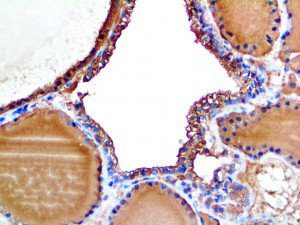

This activation induces inflammatory monocytes to highly express IL-6, starting a localized and then systemic cascade effect that results in hyperproduction of IL-6, which accelerates the inflammatory process. Because IL-6 also increases vascular permeability, excessive levels cause blood vessels to become very leaky. This, along with clotting factors released from vascular endothelial cells, stimulates the coagulation cascade, resulting in microthrombosis (tiny clots), which leads to ischemia and tissue death of the kidney, intestines, heart, liver, brain and extremities.